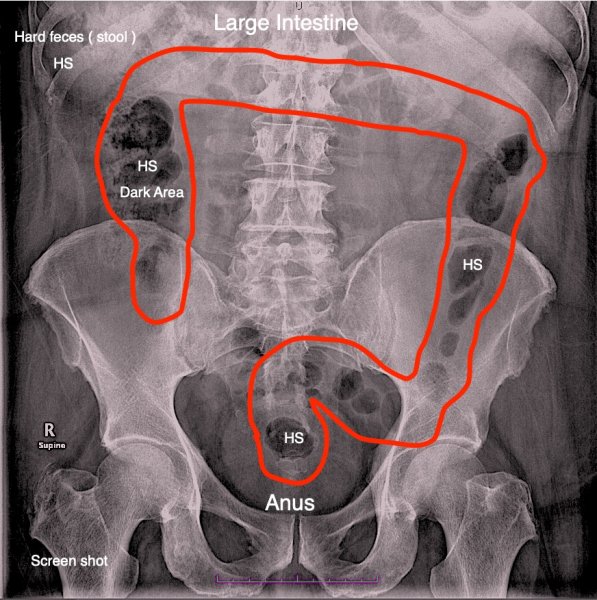

1. Hi Sheryl I thought I would update my situation and hopefully get your thoughts. On returning back to the Suranaree University of Technology Hospital in Korat , on the 1st of March 2026 , to hear the results of the colonoscopy and a gastroscopy tests from the gastroenterologist. In the gastroenterologist office, I told him that I was still suffering from on going daily constipation , and had continued to take a range of laxatives. The gastroenterologist then showed me on his computer screen the results from my past CT scan. One view of the CT scan that the gastroenterologist showed me , was my large intestines ( see the screen shot ) . The CT scan view shown in the screen shot , shows my large intestines and several areas where it appears to show where there are feces blockages ( hard stools - the dark areas ) the medical term is fecal impaction . The gastroenterologist on looking at the CT scan shown in the screen shot , did not seem too concerned about the feces ( dark areas ) even though I had told him that I was still suffering from daily constipation. The gastroenterologist on reviewing the CT scan ( shown in the screen shot ) said that he was going to prescribe one drug that should help with my on going daily constipation , that drug costs 45 Baht for one 5mg pill and is called ‘’ Goofice ‘’ ( Elobixibat ). I asked the gastroenterologist if while taking the ‘’ Goofice ‘’ pills , was it still ok to keep taking a laxative at the same time. The gastroenterologist said Yes. So currently I’m taking the ‘’ Goofice ‘’ pills along with Two separate laxatives ( see screen shots ) . Laxative 1 – Forlax 10g Forlax 10g (Macrogol 4000)It is a water-soluble powder medicine that is classified as an osmotic laxative (Osmotic Laxative). It is used to temporarily relieve constipation in adults and children aged 8 years and up. It works through increasing the amount of water in the stool. Makes the stool softer and easier to excrete Laxative 2 – Senna Senna is a natural stimulant laxative derived from the senna plant, used for short-term relief of occasional constipation by stimulating gut muscles. Its still early days for taking the ‘’ Goofice ‘’ pills , so I don’t know the results yet. So currently I’m taking the Two laxatives and the ‘’ Goofice pills ‘’ to try and help with my still ongoing constipation problem , that so far has not stopped or dreceased. I have also tried using an enema at home ( see screen shot ) and changed my diet. My next appointment to see the same gastroenterologist is on May the 25th . So it seems that I have so far done what I can to finally eliminate my having the daily constipation , but only time will tell. Any thoughts , advice or recommendations about the above please.

2. Hi Sheryl Just an update , I went to my appointment on the 26th of January at the Suranaree University of Technology Hospital in Korat. When I arrived at the hospital I was taken to see the GP doctor who had previously prescribed 6 Sodium Chloride enema’s , that I had used but had made no difference. The GP doctor on hearing that the 6 Sodium Chloride enema’s had made no difference, said that it would be best for me to now undergo both X-Rays and a CT scan that day . First I went to the imaging department , where I had 3 abdominal X-rays taken . Then I was taken to a procedure room , where a cannula ( IV line connector ) was inserted into a vein on my right hand. After having the cannula fitted, I was taken to the CT scan department . Once in the CT scan department I was told to lie on my back on the CT scanner table . After lying on the CT scanner table, a clear tube was inserted into my anus , the tube was connected to a clear plastic bag hanging from an IV bag stand . Then an IV line was connected to the cannula on my right hand, and I was told to raise both arms above my head , so the CT scan could begin. After undergoing the CT scan , I was taken back to the procedure room , where the cannula ( IV line connector ) was removed. I was then taken to have a blood test , where the results of the blood test showed no negative numbers. Later the same afternoon I went to see a GI doctor ( gastroenterologist ) to review the results of both the 3 X-rays and the CT scan. I sat in front of the GI doctor , who spoke understandable English, the doctor then on his computer monitor screen , showed my the CT scan images , the GI doctor on the CT scan images , pointed out one small area of my stomach , where it was showing a small light gray area. The GI doctor then commented that the small gray area shown on my stomach , could be nothing to worry about ( may be the Reflux acid I suffer from ) but just to be sure the GI doctor said that it would be advisable for me to undergo a …….Gastroscopy procedure . Next the GI doctor showed me more of my CT scan , relating to me not being able to pass any hard feces ( only soft diarrhea and constipation ) The GI doctor on reviewing the CT scan results , said that it looked like I had a condition called fecal impaction . ( see screen shot A ) So the GI doctor then recommended that I undergo a …...Colonoscopy procedure . The GI doctor then said the he would make an appointment for me to have both a Gastroscopy procedure and the Colonoscopy procedure done together on the same day. The appointment the GI doctor made was for me to be admitted to the Suranaree University of Technology Hospital in Korat, on Saturday the 31st of January and have both the Gastroscopy procedure and the Colonoscopy procedure done the next day on Sunday the 1st of February , staying only 1 night in the hospital . I decided to stay in a 400 Baht a day ward option ( see screen shot B ) it was a small air conditioned ward with only 6 beds ( only 3 beds were occupied ). On Saturday evening at 8 Pm, a nurse came to see me and said that I had to drink all the green liquid in the plastic container ( see screen shot D ) within 2 hours , this green liquid was a laxative to help with the coming Colonoscopy procedure ,the next day . After drinking all the green liquid I had to show the nurse , what type of bowel movement I had experienced , by pointing out a number on a chart ( see screen shot E ). The next morning ( Sunday ) I was taken into the room where both the Colonoscopy and a Gastroscopy were to be performed. The room seemed to be fairly new looking , and all the equipment looked like it was all new. A mouth guard was placed in my mouth and I was quickly put to sleep. When I awoke from undergoing both the procedures , I was taken back to the ward where I had stayed the previous night. Some time later a nurse came to see me and said that I had to now eat some thing ( rice and minced pork soup ) to see if eating any food produced stomach pains . I ate the soup and told the nurse that after eating the soup , I had not experienced any stomach pains at all. Later in the afternoon a doctor came to see me, and he explained that he was the GI doctors assistant , and I would need to return back to the hospital in one months time , to see the GI doctor who would then give me the results from the colonoscopy and a gastroscopy tests I had just undergone . I asked the GI doctors assistant doctor , why I could not be given the results of the colonoscopy and a gastroscopy tests , I had just undertaken , much sooner. The GI doctors assistant doctor said that a biopsy had been taken while undergoing the gastroscopy test which would take some time to get the results , also the GI doctor was going to prescribe me a month’s worth of some thing called Mucilin SF ( see screen shot F ) and the GI doctor wanted to hear how I got on with taking the Mucilin SF, for one month. I asked the GI doctors assistance if he could tell me any thing about the results of my colonoscopy and a gastroscopy tests . The GI doctors assistance, then looked at his paperwork and said that overall there was nothing found during those colonoscopy and a gastroscopy tests, that was a cause for concern. As for the colonoscopy tests , a hard fecal / feces blockage was located and removed, so hopefully that will help with my past constipation problem. So now I have to wait for a month , to hear the final results of the colonoscopy and a gastroscopy tests and the biopsy test , which feels a bit nerve racking . As for my stay and medical treatment while at the Suranaree University of Technology Hospital in Korat, I have to say that the medical care was excellent and very professional and I have no complaints what so ever. The total cost for undergoing both the colonoscopy and a gastroscopy tests along with all the the nursing and doctors fees and all drugs and 1 nights hospital stay , came to 15,960 Baht . I have obtained all the CD copy’s for the all the tests I underwent . I will post back when I hear the test results on the 1st of March .